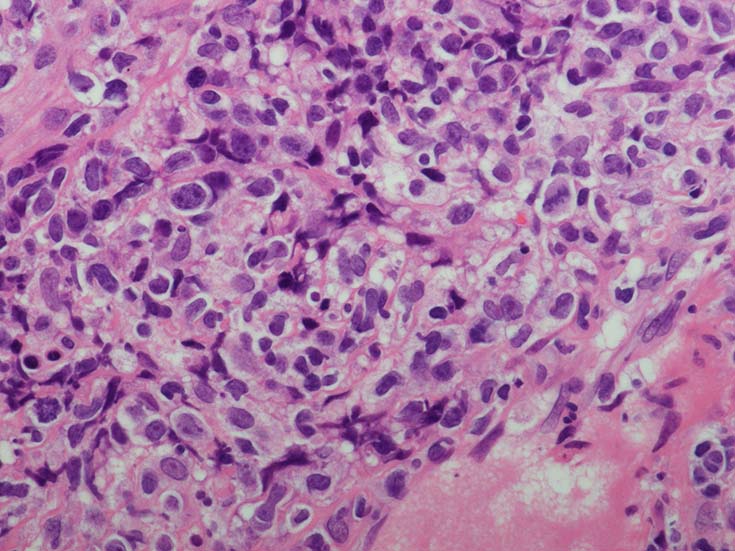

EBUS-GS(ガイドシース併用気管支腔内超音波断層法)による肺生検組織病理所見.

血管周囲性に大型類円形核や不整形核をもつ腫瘍細胞がシート状密に浸潤増殖している. Mitosisが多く認められる.細血管閉塞や破壊の所見がある.

間質にもシート状の腫瘍細胞浸潤がある. 大小 pleomorphicな傾向.(A, B). necrosisが認められる(C). 細気管支上皮直下まで密な浸潤あり, 小型リンパ球が混在している.(D)

血管中心性浸潤. 障害された血管内に血栓が形成されている.CD20陽性細胞がシート状密に浸潤, CD3陽性T細胞が多く混在している. EBER-ISH陽性 EBV感染細胞が多数認められ, >50 hpf, 定義より Grade3となる. 陽性細胞のサイズは大小さまざまであることに注意.